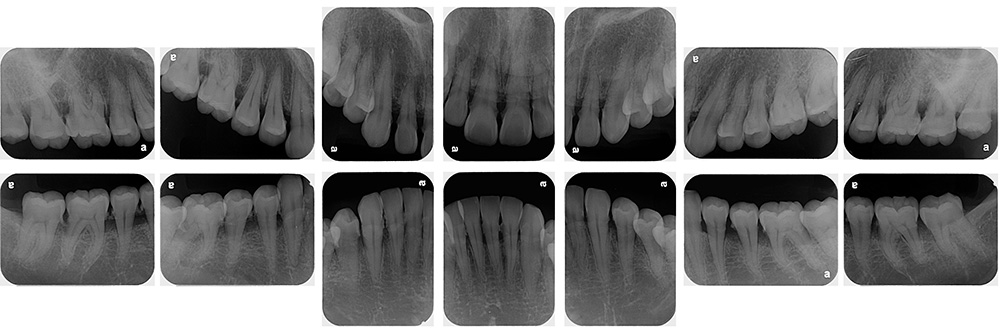

症例

症例紹介

治療方法

お悩み

術前

術後

世代・性別

20代女性

主訴

歯ブラシで歯茎から血が出るので見てほしい

治療内容

ブラッシング指導、虫歯治療、歯周基本治療、智歯抜歯

治療期間

6ヶ月

治療費

保険適応内

治療のリスク

治療後にしみる・痛みが出ることがある